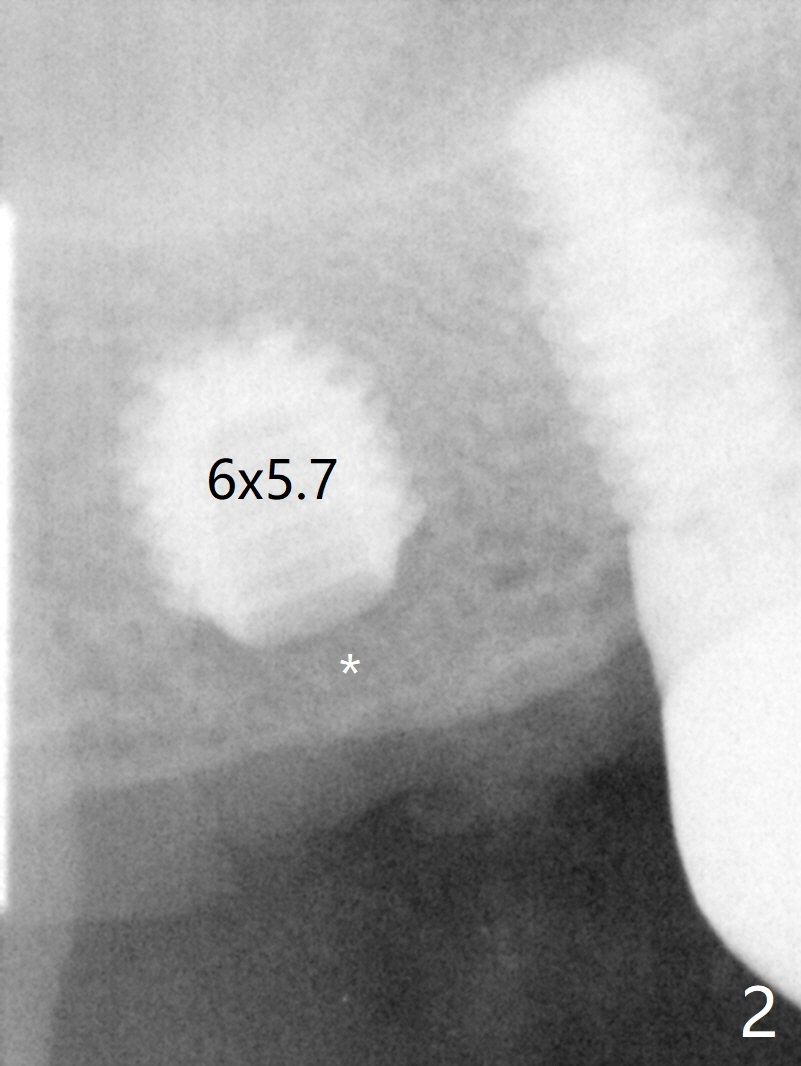

A 70-year-old man agrees to have an implant to be placed at the site of #2 (Fig.1). A 6x5.7 mm implant is placed ~ 3 mm subcrestal and covered by autogenous bone coronally (Fig.2 *). The implant plateau is surrounded by the bone 5 years 4 months post cementation (Fig.3 arrowheads). The implant fins are fully protected. Equally amazing is no history of screw loosening in spite of off-center placement of the implant.